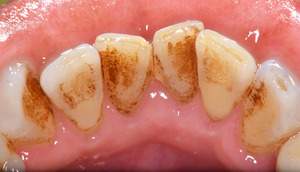

歯石除去

治療前

治療後

| 年齢 | 60歳・男性 |

| 主訴 | 歯石を取りたい |

| 治療内容 | 歯石除去 |

| 治療期間 | 30分 |

| 費用 | 約2,000円 |

| リスク・副作用 | ・歯ぐきの炎症が強いと歯石を取る際に出血することがあります ・処置後に歯がしみることがあります ・歯と歯の間に隙間ができるので、息が漏れ発音しにくいと感じることがあります ・歯ぐきの炎症が軽減すると歯ぐきが引き締まり、歯が長く見えることがあります |